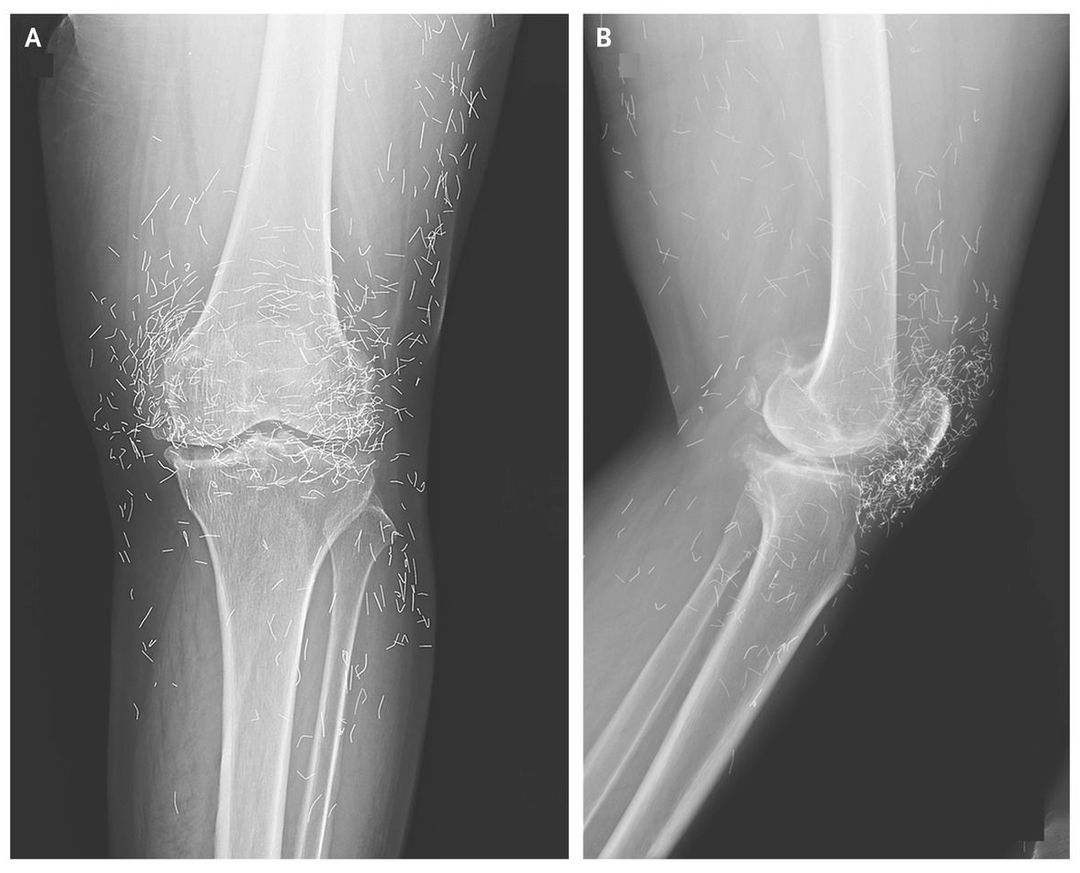

A 65-year-old woman presented with pain in both knees. She had received a diagnosis of osteoarthritis of the knee previously and had been treated with analgesic agents and nonsteroidal antiinflammatory drugs. In addition, she was treated intermittently with intraarticular injection of a glucocorticoid. In spite of these therapies, the arthralgia in the knees did not abate. Gastrointestinal discomfort caused by the medications necessitated their discontinuation. Therefore, she underwent acupuncture with gold threads as an adjunctive therapy once per week and more frequently when severe pain was present. Radiography of the left knee revealed moderate subchondral sclerosis of the medial portion of the tibia, osteophytosis of the medial portions of the tibia and femur with possible narrowing of the joint space, and numerous radiodense threads around the left knee joint (Panel A shows the anteroposterior view, and Panel B the lateral view). Complementary medicine and alternative medicine are often pursued in the treatment of osteoarthritis. Acupuncture is widely used as a treatment for painful joints. It has been hypothesized that gold thread implanted at the acupuncture points acts as a continuous acupuncture stimulation. The insertion of small pieces of sterile gold thread around the joint by means of acupuncture needles has been used commonly in the treatment of osteoarthritis and rheumatoid arthritis in Asian countries. Gold threads may complicate radiographic assessment, as seen here.